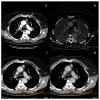

Dual-energy computed tomography (DECT) is one of the most promising technological innovations made in the field of imaging in recent years. Thanks to its ability to provide quantitative and reproducible data, and to improve radiologists' confidence, especially in the less experienced, its applications are increasing in number and variety. In thoracic diseases, DECT is able to provide well-known benefits, although many recent articles have sought to investigate new perspectives. This narrative review aims to provide the reader with an overview of the applications and advantages of DECT in thoracic diseases, focusing on the most recent innovations. The research process was conducted on the databases of Pubmed and Cochrane. The article is organized according to the anatomical district: the review will focus on pleural, lung parenchymal, breast, mediastinal, lymph nodes, vascular and skeletal applications of DECT. In conclusion, considering the new potential applications and the evidence reported in the latest papers, DECT is progressively entering the daily practice of radiologists, and by reading this simple narrative review, every radiologist will know the state of the art of DECT in thoracic diseases.